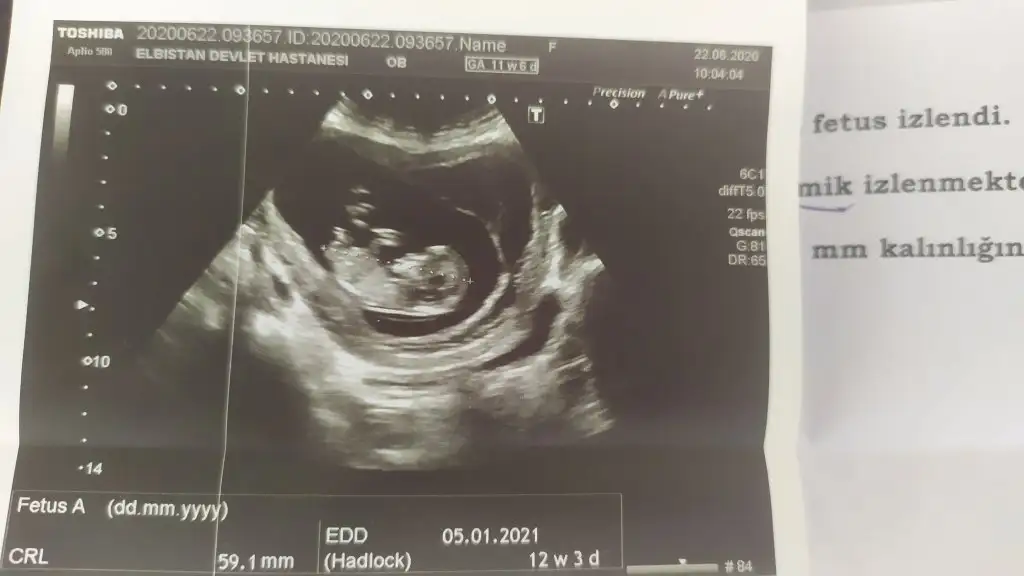

Erkek gibi sanki 13 hafta usg de paylaşınMerhaba 11+0 günlük usg yorum yapabilir misiniz

Doktorumuz kıza benzetti bakalım hayırlısı öğrenince pylaşırım☺ Birkaç usg daha var onları da ekliyorumErkek gibi sanki 13 hafta usg de paylaşın

Net değil 12-13 hafta olursa paylaşınDoktorumuz kıza benzetti bakalım hayırlısı öğrenince pylaşırım☺ Birkaç usg daha var onları da ekliyorum

Kız sanki emin olamadım başka usg de paylaşınBanada tahmin yapabilirmisiniz 12 haftalık